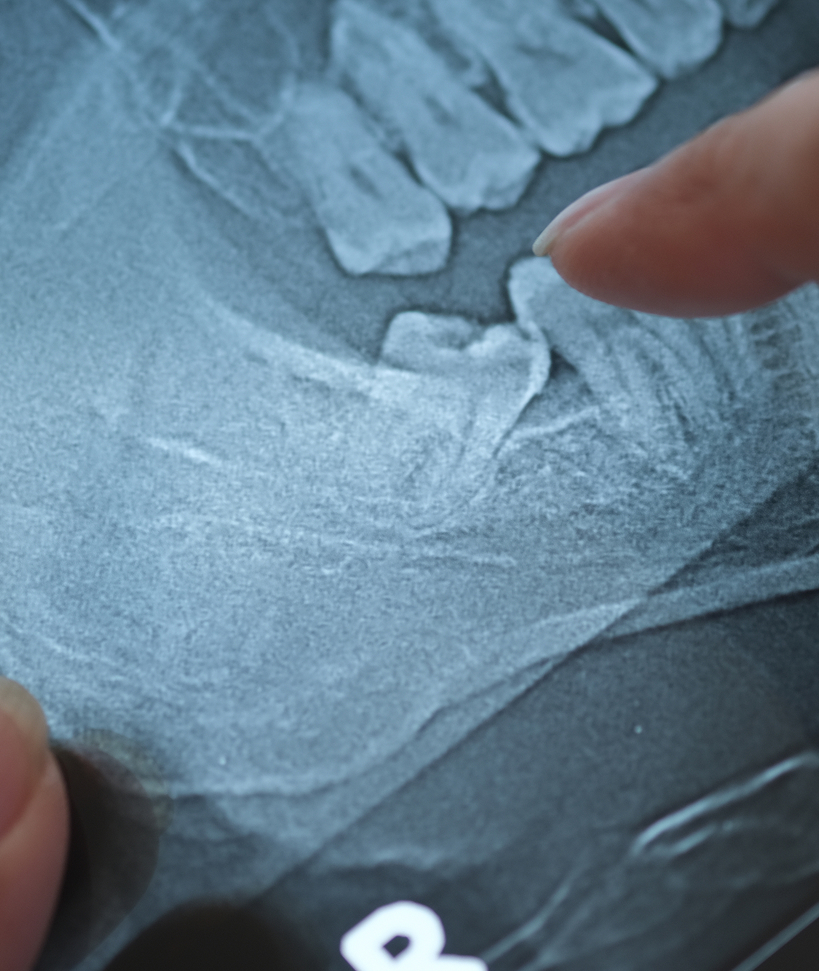

Extraction des dents de sagesse

Les dents de sagesse apparaissent généralement à l’adolescence ou au début de l’âge adulte. Dans certains cas, leur positionnement peut entraîner des douleurs, des infections ou des complications orthodontiques.

L’extraction est souvent recommandée lorsque :

- Les dents sont incluses ou partiellement sorties de la gencive (semi-incluses) ;

- Elles causent une pression sur les autres dents, entraînant potentiellement un désalignement et des dommages ;

- Il y a des infections ou des douleurs récurrentes.